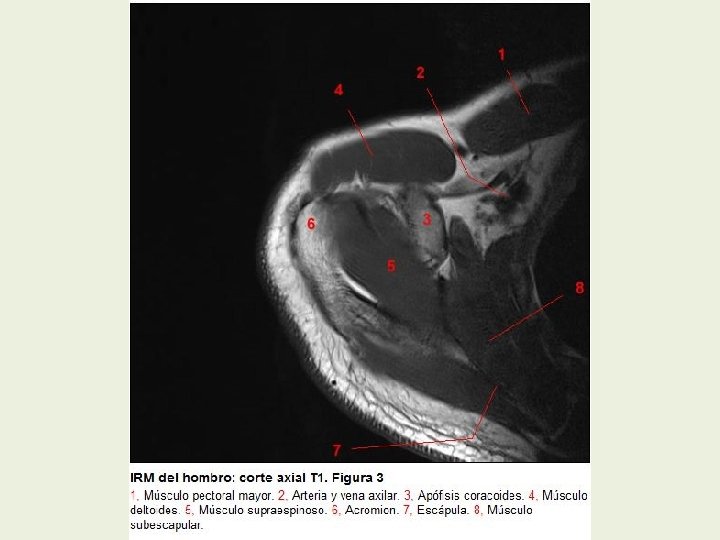

Hombro Cortes axiales RMN